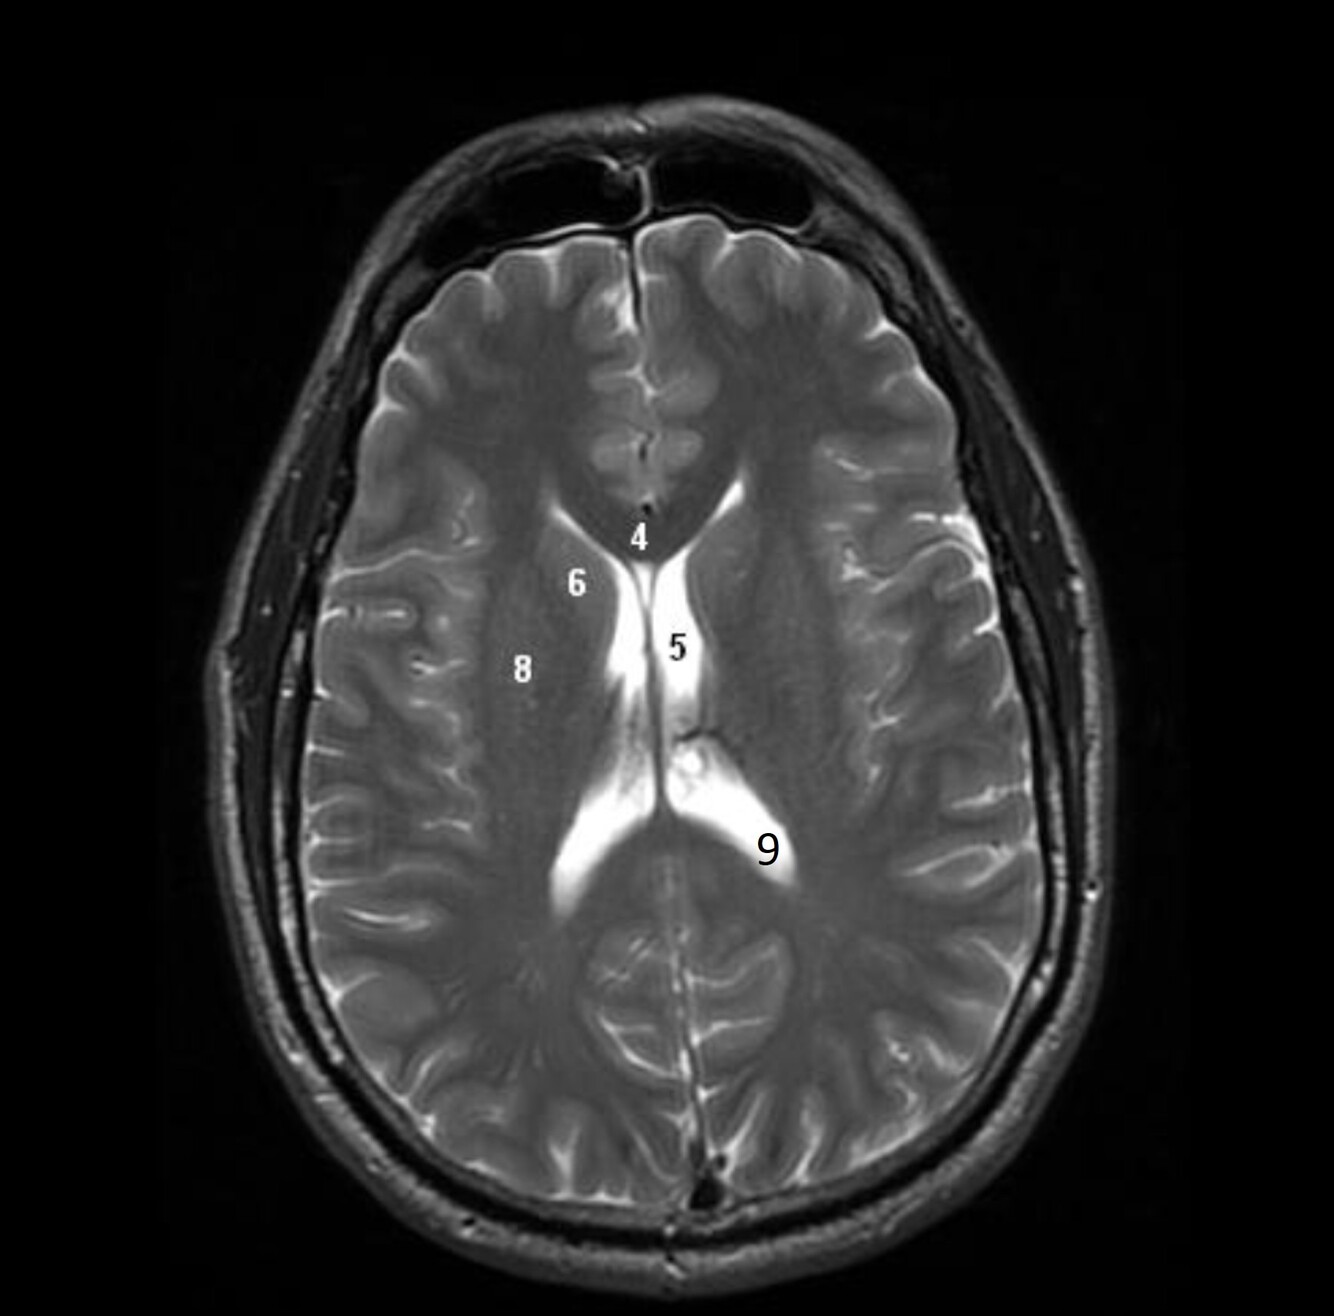

Label 4,5,6,8,9

4=Genu, CC

5=Lt lateral ventricle (body)

6=Head of Rt caudate nucleus

8-Rt Lentiform nucleus

9=Lt lateral ventricle (post. horn)